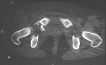

Radiographs:

Radiographs revealed a vertical buckle fracture of the right inferior sacrum, oblique fractures of the superior and inferior rami on the right and a fracture through the medial acetabulum. Obturator and iliac oblique inlet and outlet pelvic views, and a thin cut CT with 3-D reconstruction of the acetabulum were performed. These elucidated a comminuted anterior wall with fracture line extending to the posterior column. The posterior column was non-displaced. The pelvic fracture was non-displaced.

1. Right T-shaped acetabular fracture with anterior wall comminution.